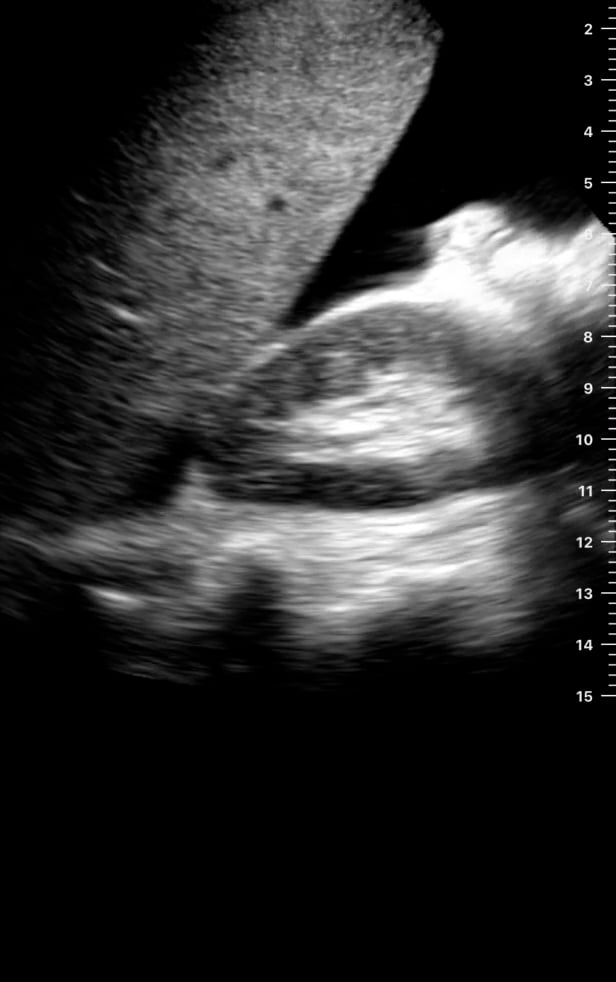

Morrison’s pouch, or the hepatorenal recess, is a crucial anatomical space located between the liver and the right kidney. In the context of FAST (Focused Assessment with Sonography for Trauma) exams, this area is a critical site for detecting free intraperitoneal fluid, such as blood, in trauma patients. Its dependent position makes it one of the first places fluid accumulates when internal bleeding occurs, making rapid ultrasound assessment here vital for diagnosing significant abdominal injuries.

For medical ultrasound professionals, understanding Morrison’s pouch is key to efficient and accurate trauma evaluation. Identifying fluid in this space on ultrasound images can indicate a life-threatening hemoperitoneum, guiding immediate clinical decisions and interventions. This rapid, non-invasive assessment enhances patient care and outcomes in emergency and trauma settings, highlighting the indispensable role of point-of-care ultrasound.